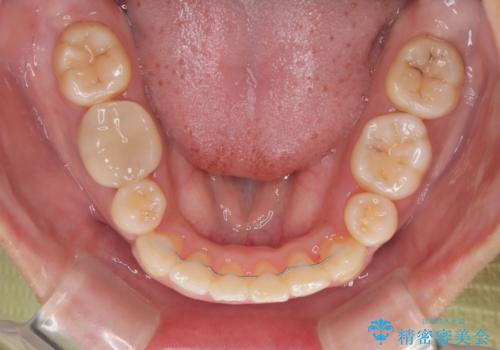

口元の突出感が改善されてことで、下唇に引っかかっていた上顎前歯も気にならなくなりました。

上下前歯がくちばしのように突出していたため、上下左右の第一小臼歯4本を抜歯し、ワイヤー装置にて矯正治療を行うこととしました。